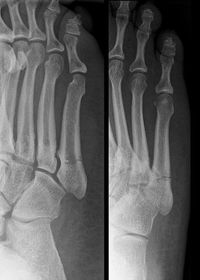

| What do these images show? What is this disease called? How does this differ from Meuller Wiess Syndrome? | Osteochondrosis of the navicular. Kohler's disease. Kohler's disease only appears in children, Meuller Wiess Syndrome only appears in adults and is a spontaneus osteonecrosis of the navicular, not a true osteochondrosis. |